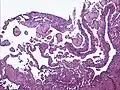

Low power photomicrograph of an endovascular papillary angioendothelioma showing papillae with hyalinized cores

Low power photomicrograph of an endovascular papillary angioendothelioma showing papillae with hyalinized cores High power view showing a vascular tumor with cuboidal endothelium lining the vessels. Few entrapped seminiferous tubules are also noted (arrow).